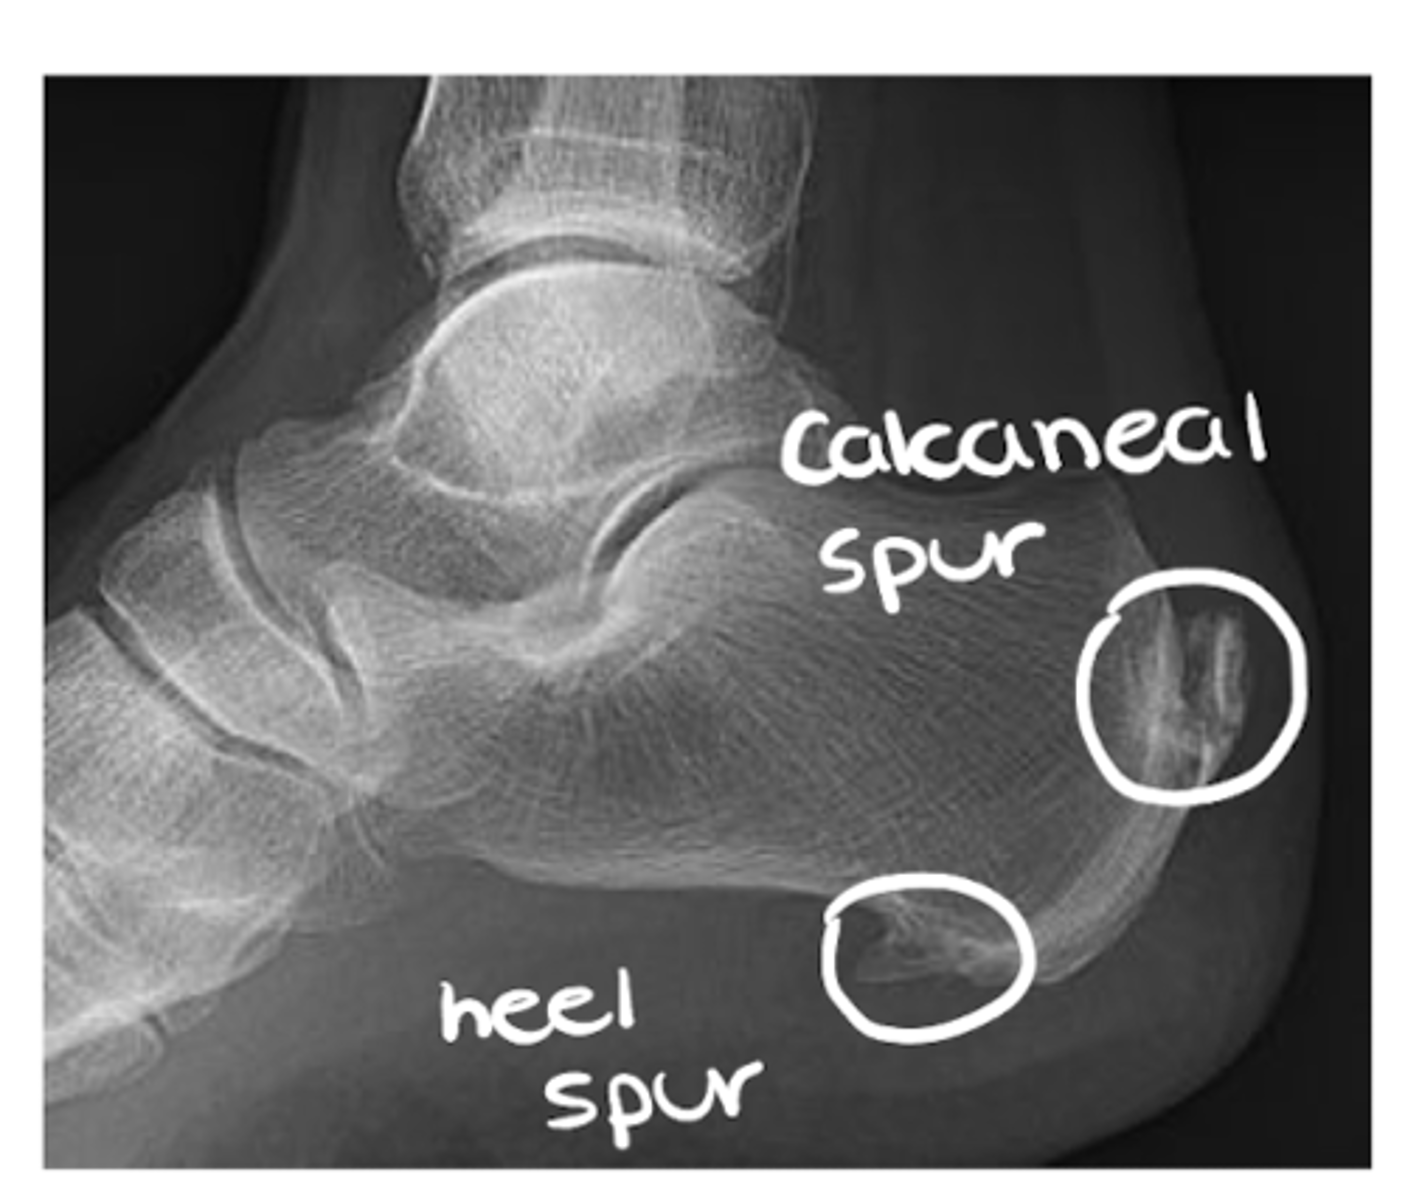

List the sub-components of (A) alignment: general contour

- Spurs and osteophytes

Hardening of the bone tissue at the joint line (often a primary indicator of OA)

Loss of cartilage (primary indication of OA, along with bone spurs and sclerosis)